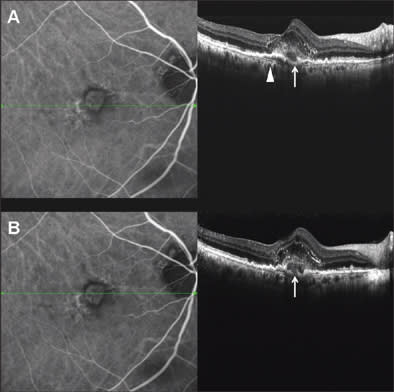

A 68-year-old man with a 3-year history of exudative age-related maculopathy had been treated with photodynamic therapy in his right eye 2 years before and recently presented reactivation of the lesion. Best-corrected VA was 20/63. In Figure 2, we can see the subfoveal CNV analyzed with simultaneous SD-OCT and ICGA. The line along the ICGA images represents the exact location of the OCT scan line. In SD-OCT images, the vascular net organization is visible, and under neovascularization, Bruch's membrane (arrow head) is easy to identify as a continuous, hyperreflective band, separating from the RPE layer.

Figure 2. Subfoveal choroidal neovascularization, analyzed with SD-OCT and simultaneous ICGA. Internal structure of the CNV and photoreceptor alteration are visible in SD-OCT images. BM is definite and continuous as a hyperreflective band separating from RPE (arrow head). Choroidal vessels are sharp and identifiable. Very little translation of scanning position between top panel and bottom panel reveals the presence of RPE disruption (white arrow).

A very little shift of scan line position between the top panel and bottom panels allows us to identify a disruption on the RPE layer (white arrow), not visible in the top panel and clearly distinguishable in the bottom panel. This is probably the point of penetration of new vessels from choroidal to retinal space. Even intraretinal elements are well visible: The external limiting membrane is a continuous, hyperreflective, thin band that follows the shape of the underlying alterations. Moreover, photoreceptors over the CNV appear altered, as a hetereogeneous, thickened layer under the inner limiting membrane.